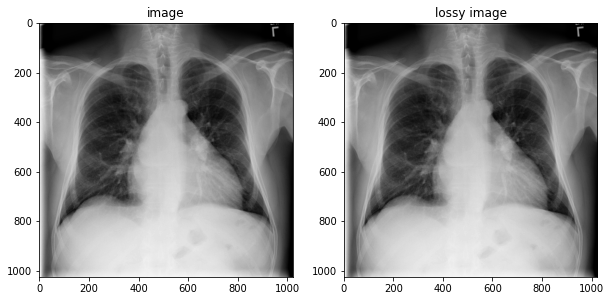

fig, axes = plt.subplots(1,2, figsize=(10,10))

axes[0].imshow(np.squeeze(image.numpy()), cmap='gray')

axes[0].set_title('image')

axes[1].imshow(np.squeeze(lossy_image.numpy()), cmap='gray')

axes[1].set_title('lossy image');